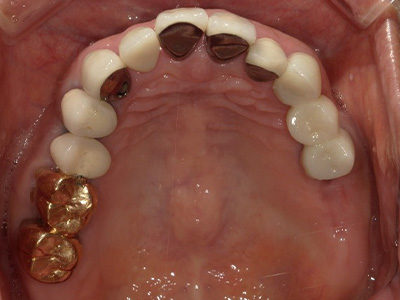

見た目も噛み心地も妥協しない

「補綴主導型インプラント」

一切妥協しないインプラント

最終的な被せ物(補綴)の理想的な形・位置から逆算し、インプラントを噛み心地と見た目に最適な位置に設計・埋入します。

技工士と院長が共同で設計し、その中心に正確にインプラントを配置。自然な見た目と快適な噛み心地の両立が可能になります。